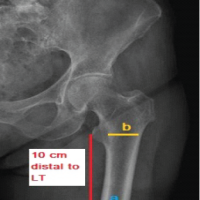

The patient was positioned in a beach chair at a 30° incline (Fig. 1A), and the surgical site was prepared under sterile protocols. Fractures were initially reduced using closed techniques and temporarily stabilized with K-wires before employing a minimally invasive approach for definitive fixation. Longitudinal traction was applied to the humeral shaft with the elbow flexed at 90° to correct displacements and angulations. The shoulder was adjusted internally and externally until the proximal and distal fragments aligned (Fig. 1B), maintained with a Kirschner wire. The greater tuberosity was reduced using a K-wire as a joystick (Fig. 1C), while significantly fewer tuberosity fragments were secured with a separate interfragmentary screw. Fixation was then performed using a locking plate and screws via the MIPPO technique (Fig. 1D-L).

Figure 1: (A) Patient position – beach chair, (B) Fluoroscopy confirmation, (C) Temporary k wire fixation, (D) Proximal incision, (E) Sub-muscular tunnel using blunt dissection, (F) Plate insertion, (G) Plate position under fluoroscopy, (H) Proximal locking screw fixation, (I) Distal incision marking, (J) After both incision, (K) Final fluoroscopy image anteroposterior view, (L) Final fluoroscopy image lateral view.